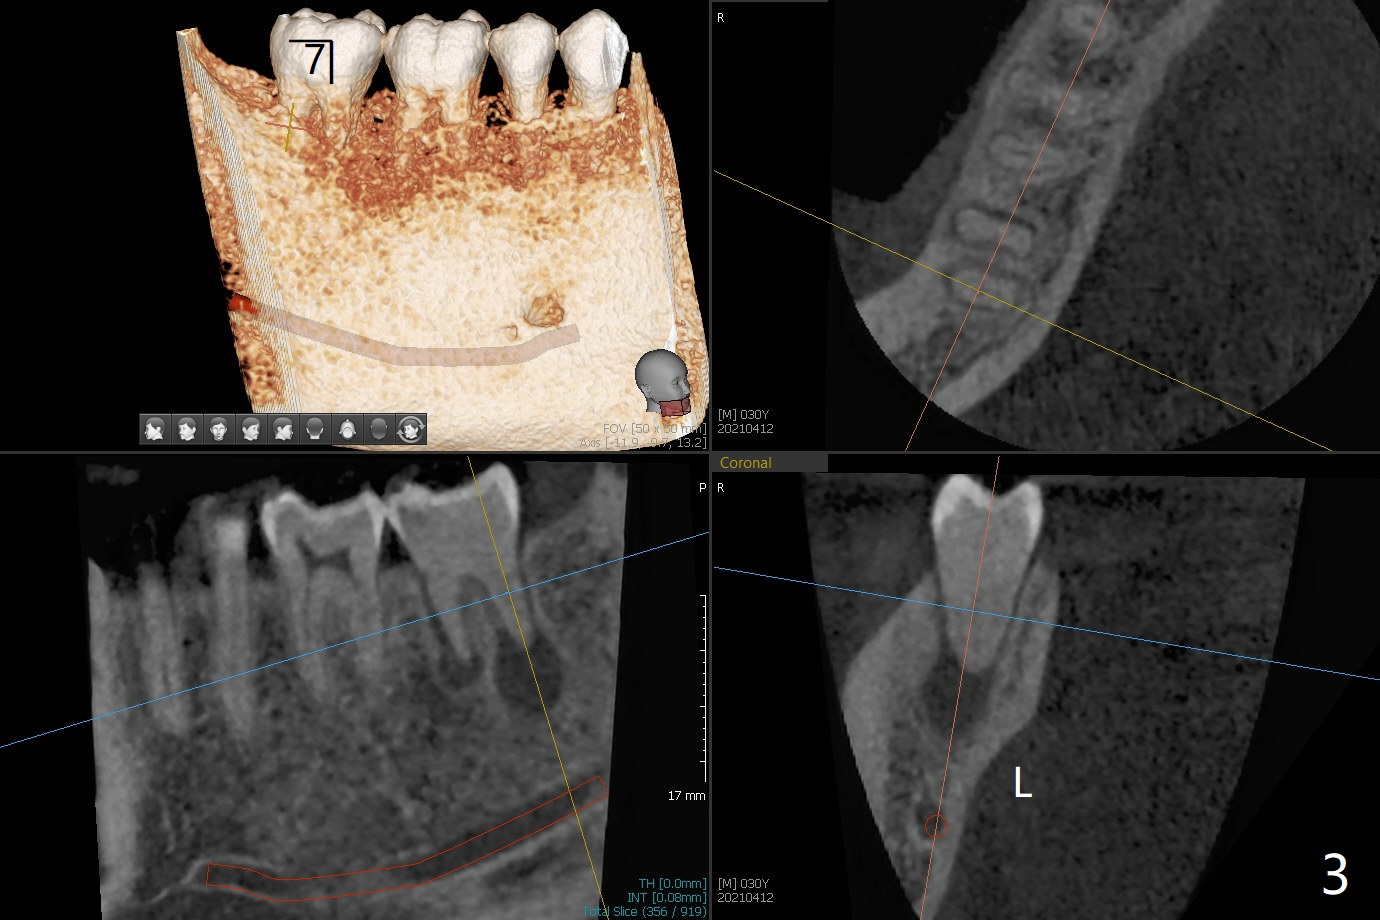

30岁男小的时候双侧下颌第二磨牙埋伏,拔除智齿后,前者经过矫正才萌出。近几年两个第二磨牙都出现疼痛,牙髓病专家认为左侧预后不佳(图一),需要拔除种植(图二)。注意去除根尖肉芽组织。左下7治疗完成后病人要求右下7拔除植牙(图三,四)。